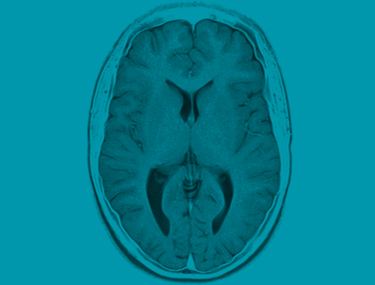

Definition: Im Unterschied zum konventionellen Röntgen arbeitet die Kernspintomographie mit starken Magnetfeldern, weswegen mit dieser Methode andere Strukturen als im herkömmlichen Röntgenbild sichtbar gemacht werden können. Gerade auch im Bereich der Sportmedizin ist deswegen diese Methode inzwischen zum unverzichtbaren Standard bei der Abklärung von Sportverletzungen geworden.

Das MR liefert auch bildgebende Information über Weichteile. Gerade im Gelenksbereich werden neben dem knöchernen Skelett auch Strukturen wie Bandapparat, Sehnen, Gelenkskapsel, Knorpel, Meniscus, Muskel bildhaft in mehreren Ebenen abgebildet. Ebenso können bei Unfällen verletzungsbedingte Flüssigkeitsansammlungen wie bei Gelenkserguss und Schwellung durch Einblutung im Weichteilmantel dargestellt werden. Ein Quantensprung in der prezisen Findung einer Diagnose – damit wird bei Verletzungen im Gelenksbereich das MRI zum Goldstandard in der Sportmedizin.